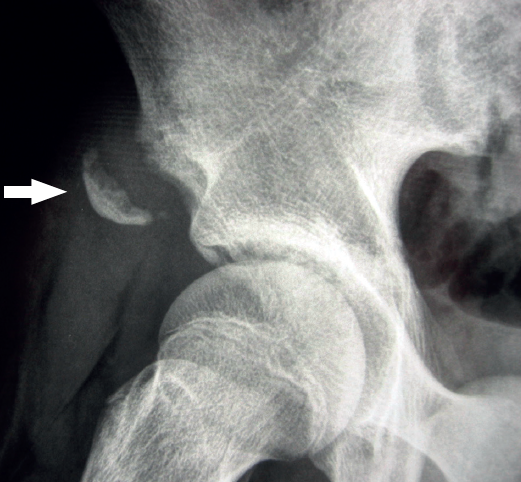

Figure 6. Alar radiographic view of the right hip of an adolescent. Apophysiolysis of the anterior inferior iliac spine secondary to traction of the tendon of the rectus femoris of the quadriceps. The arrow indicates the avulsed bone fragment.

If the pain is located very proximal, it is important to remember that tearing of the tendon may occur at its origin in the anterior inferior iliac spine (AIIS), with or without associated bone avulsion (Figure 6).